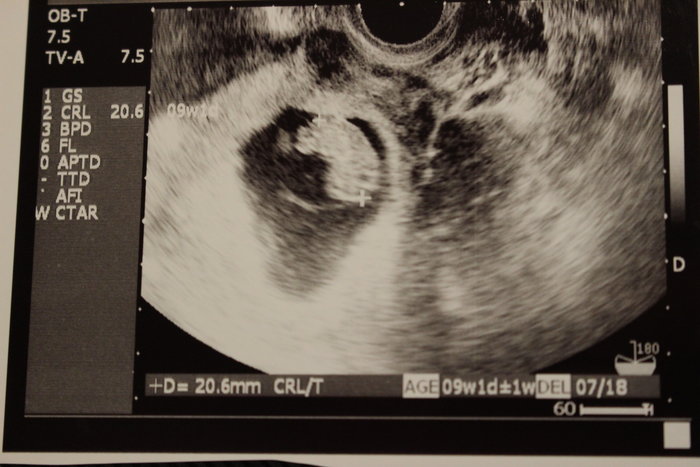

胎芽が見えない 健診に行って胎芽が見えないと不安になりますよね。 一般的に胎芽が確認される時期は妊娠6週頃が多いです。 しかし個人差があって早い人では妊娠5週後半、遅い人は妊娠7週頃と幅があります。 胎のうが確認できて胎芽が確認できないと不安が大きくなりますが、焦らずに次の健診を待つことが必要です。テーマ: ブログ 昨日、妊娠7週3日の胎嚢の大きさだけど、赤ちゃん見えてこない 来週もっかい受診して見えなければ流産、 と診断を受けて2日目。 基礎体温下がらず。 昨日に引き続き、つわりが消えました。 あんなに気持ち悪かった「胎芽見えない」 「胎嚢空っぽ」 を検索しまくりました 7週目でやっと赤ちゃんが見えた人も結構いる まだ希望を捨てたら早いよね お腹にまだ赤ちゃんいるよね 旦那さんに『赤ちゃんがいないかもしれない』と話しました 冷静に『信じて待つしかない

現在妊娠7週目です。 胎嚢は大きくなっていますが、 胎芽が見えない状態です。 9週目頃に再診して胎芽が見えなければ 稽留流産と言われています。 成長がゆっくりなのか判断が難しいとのことでした。 まだ望みを捨てきれていないのですが、見てみて見えないようであれば 今回は流産と言うことで。と 言われる。可能性は50/50だと 言う感じでした。 実際排卵がずれていなくて 最終月経から数えると、 6/6の時点で7週 5/23日の時点で胎嚢が見えなかった のが排卵がずれていたからとして 23日を4週だとするとなんだか朝から今日はあんまり気持ち悪くないぞ。 昨日基礎体温が363℃に下がってたけど、今朝は369℃だった 7週目、赤ちゃん見えない My home and diary

妊娠7週以降で胎嚢は見えているのに胎芽やその 心拍が確認できなかったり、一度は確認できた心拍が消えてしまった場合には、「 稽留流産 」の可能性があります。妊娠検査薬で陽性だったけど、病院へ行くと 「胎嚢が見えない」 、 「胎嚢はあるけど胎芽が確認できない」 といわれた。 胎嚢は早ければ妊娠4週のはじめに確認でき、一般的には 妊娠4週末から妊娠5週頃 までに見えます。 続いて胎芽・心拍が妊娠8週までに全ての妊婦さんに確認できると妊娠7週2日 胎嚢のみ 胎芽が見えない *yurire*lalaブログ 〜ファッション、子育て、好きな事〜 17年08月17日 1029 昨日、産婦人科に行ってきました主人もお休みだったので、心拍確認出来るのを楽しみに行ったんですが、診察の結果、エコーで見れたのが

でも6週でまだ確認できない人もいる。 6週で何も見えなくて7週8週でやっと心拍確認できた、という書き込みもちらほら見ました。 うちの病院のパンフレットにも「心拍確認7週目」と書かれています。 だから、来週が本当の山、リミットになるのでしょう。「7週 心拍確認」 「7週 胎芽見えない」 「7週 胎のう」 色んなワードで検索してみた。 心拍の確認は、5週半ば~6週半ば。 それより後に確認される場合もあるけれど、 それは、殆どは、週数の数え間違い。妊娠5週初期では、まだ超音波検査の画像では赤ちゃん(胎芽)が見えていないことが多いです。 妊娠5週後半になると、赤ちゃんが見え始めてきます。 妊娠6週の⼤きさ 胎嚢は15cmほどになり、胎嚢の中の白っぽい円も大きくはっきりと見えるようになり

妊娠4週になると見えてくる、「胎嚢」「卵黄嚢」って何? 妊娠5週になると脳や神経、心臓など臓器、それに手足や目、耳の原型もできるってホント? 妊娠6~7週で、心臓の動き出す!? まだ「胎児」と呼んでもらえない妊娠2ヶ月の「胎芽」時代の赤ちゃんのこと、母体のこと。5週目の胎嚢の直径は5〜15mmくらいです。 5週後半くらいから約2〜3mmの胎芽 が見え始めます。 妊娠6週の⼤きさ 胎嚢の直径は約10〜25mmで10後半mm前後が平均です。 胎芽は妊娠6週後半になると6mm程度になります。 妊娠7週の⼤きさ7週3日の昨日 病院に行くと、胎嚢が13ミリになっていて 私には はっきり胎芽が見えましたが 医者は、胎芽とはまだ言えない なぁ。 少し点滅してるように見えるけど、13ミリで 心拍が見えた事は今までない ミリくらいにならないと 何とも言えない